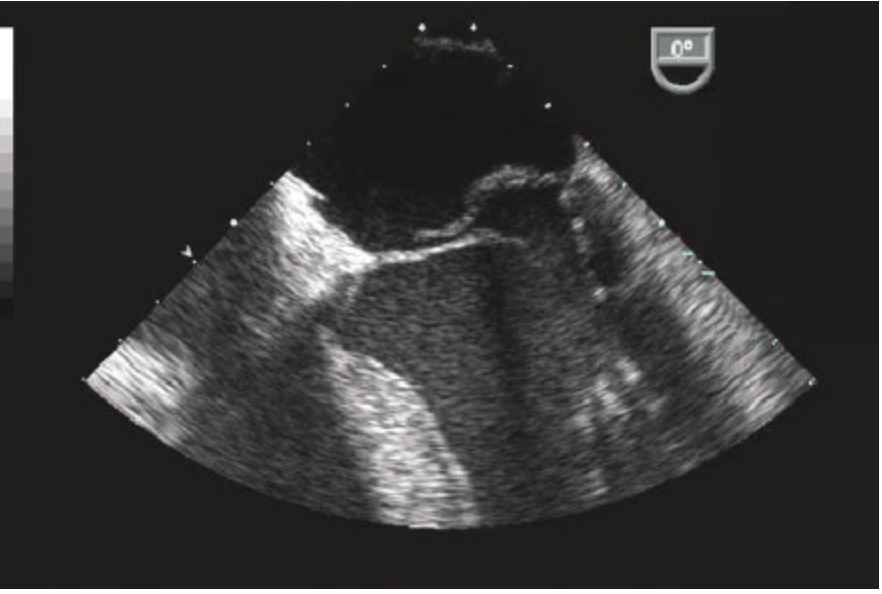

Q

What is the finding in this patient with back pain?

A

This is an example of an aortic dissection flap of the descending thoracic aorta with associated pleural effusion. Note the characteristic intimal flap that separates the true from the false lumen. The presence of a pleural effusion may represent a contained rupture but more often this represents an inflammatory pleural reaction. In patients with associated ascending aortic dissection with involvement of the aortic valve, pleural effusion may also indicate congestive heart failure.